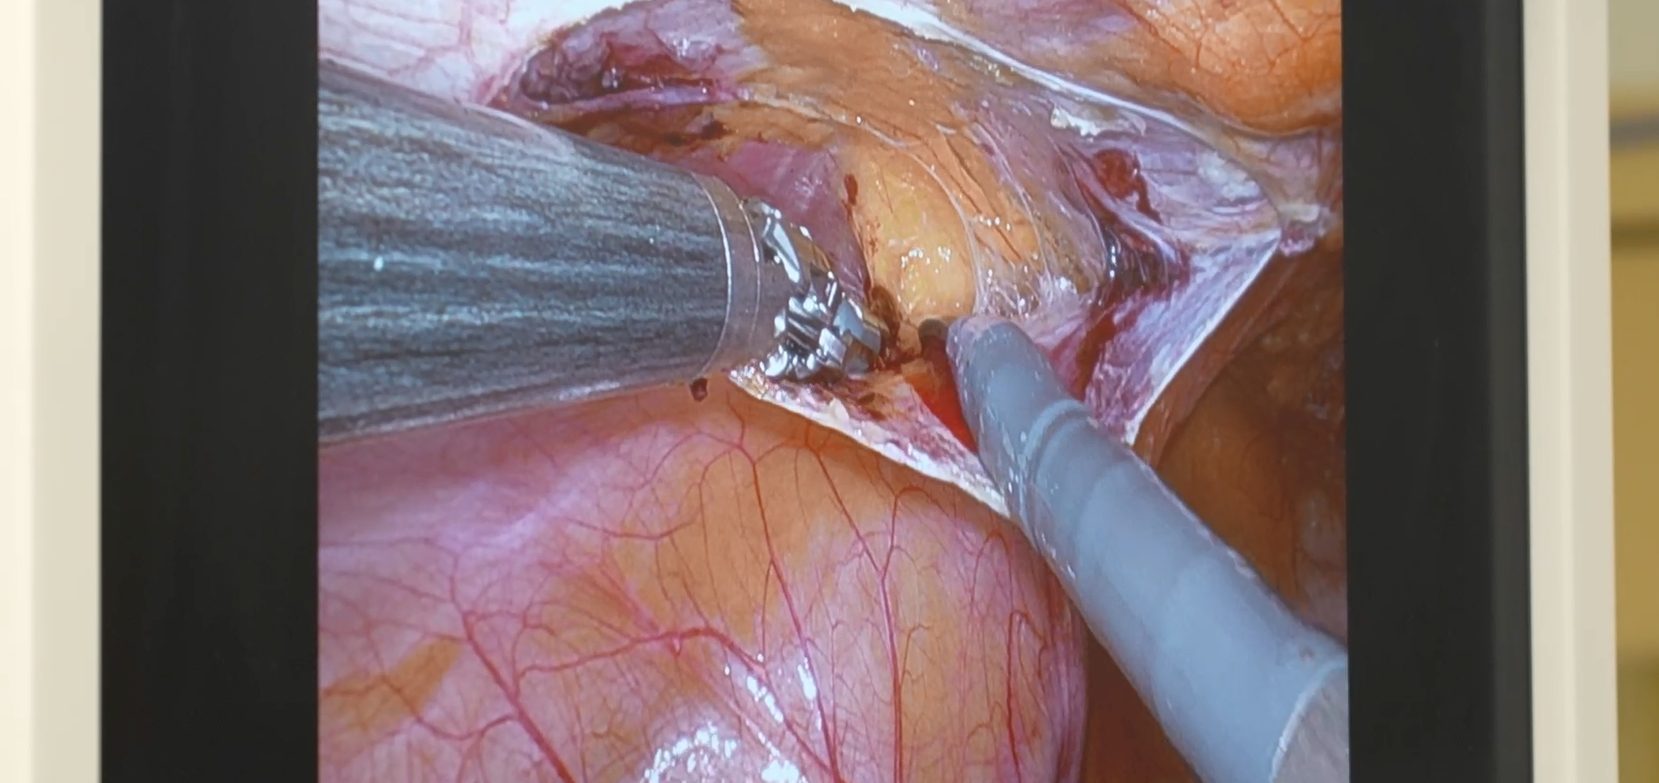

El robot Da Vinci Xi está compuesto por tres unidades principales: la consola del cirujano, el carro quirúrgico y la torre de visión. Desde la consola, el cirujano controla los instrumentos con movimientos digitalizados que eliminan temblores, garantizando precisión y ergonomía. El carro sostiene los brazos quirúrgicos, mientras que la torre de visión centraliza el procesamiento y la visualización en 3D.

Según Juan De Diego, jefe del servicio de Cirugía, las primeras intervenciones se realizaron en cirugía general y del aparato digestivo con resultados exitosos. La incorporación progresiva permitirá ampliar el uso del robot a especialidades como urología y ginecología, manteniendo la excelencia quirúrgica del hospital y reduciendo los tiempos de recuperación para los pacientes.